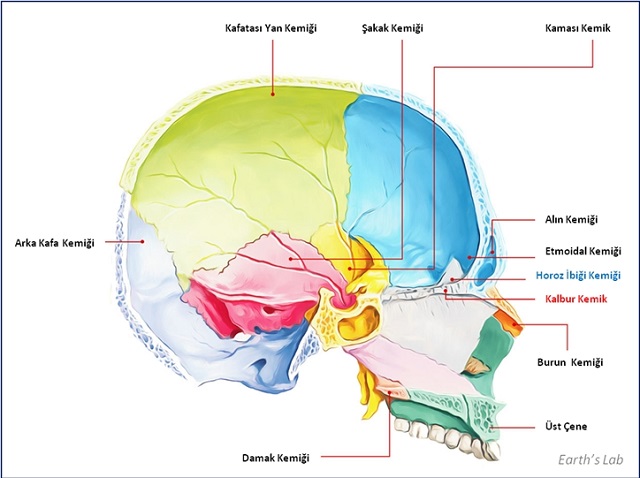

Peki, okullarda burun çubuklarını PCR testleri için kim kullanmaktadır? Ne yazık ki okul çocuklarının kendileri bu testleri uygulamaktadır. Ümit eldim ki çocuklar hata yaptıklarında fazla derine gitmemiş olsunlar. Hiç kimseye anlatılmamış gibi görünen bir ayrıntı ise aşağıdaki şekilde görülen etmoid kemiğinin kalbur şeklindeki delikli bölümü olan süngerimsi duvarın oldukça hassas, yumuşak ve bal peteği veya elek şeklinde küçük delikli ince ve dar bir yapı olduğudur. Endoskopik transnazal kafatası temelli operasyonlar için mükemmel bir giriş yeri olmasının nedeni tam da budur. Ancak, süzüntü testi için burun çubuğu kullanmakta yeteri kadar usta olmayan birinin, pamuklu çubuğu asla beyne kadar itmeyeceğini ileri sürmenin saçma bir düşünce olduğu da açıkça görülmektedir.

Doktorlar kadının burnu içinde bir kitle tespit etmişlerdir ve bu kitlenin burun çubuğu uygulaması esnasında oluşarak beyin omurilik sıvısının akıntısına neden olduğuna inanmaktadırlar. Kaynak: JAMA Otolaryngology/University of Iowa Hospitals and Clinics.